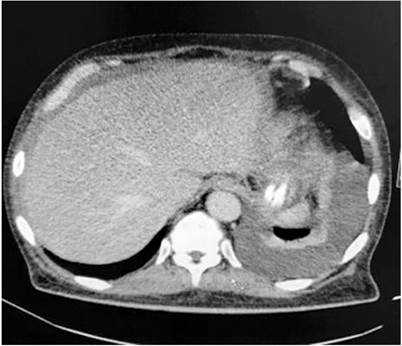

Por otra parte, para el estudio del síndrome ascítico se realiza una TC de abdomen donde se observaron lesiones de tipo omental cake. Se solicitan marcadores tumorales con reporte de CA-125 de 210 U/mL (positivo). Se realiza una paracentesis diagnóstica, cuyo líquido peritoneal mostró un patrón no hipertensivo GASA 0,7, con ADA 19,92 (negativo), cultivo y PCR para Mycobacterium tuberculosis negativos (Tabla 2). El bloque celular de líquido peritoneal reportó linfocitos con células mesoteliales reactivas y presencia de células con núcleo grande y citoplasma abundante. Todo lo anterior sugiere un proceso maligno subyacente como primera posibilidad.

El diagnóstico de TBC peritoneal suele ser difícil. Se observan hallazgos paraclínicos a nivel hematológico como anemia normocítica, normocrómica, trombocitosis y conteo normal de leucocitos. El método imagenológico de primera línea es la ecografía abdominal que evidencia la presencia de líquido ascítico y descarta la etiología portal como causa de ascitis, lo que ofrece adicionalmente una guía para el drenaje de líquido peritoneal2,17. Otra ayuda imagenológica es la TC, que en el caso de TBC peritoneal ofrece algunos hallazgos como ascitis, linfadenopatías, engrosamientos intestinales, nódulos peritoneales, adherencias, tabiques fibrinosos y un hallazgo llamado omental cake, que obliga a hacer un diagnóstico diferencial con carcinomatosis peritoneal9.

En nuestro caso se documentó el hallazgo de omental cake, condición que debido a enfermedades infecciosas es raro. Generalmente estas enfermedades resultan de diseminación hematógena, linfática o directa de microorganismos infecciosos hacia el peritoneo. Usualmente la TBC peritoneal exhibe estas manifestaciones, y la apariencia es similar a la de una carcinomatosis peritoneal. Los hallazgos que pueden ayudar a distinguirlo de una carcinomatosis peritoneal incluyen macronódulos mesentéricos, irregularidad en el infiltrado del epiplón, pared fibrosa recubriendo el epiplón infiltrado, esplenomegalia o calcificación esplénica9.